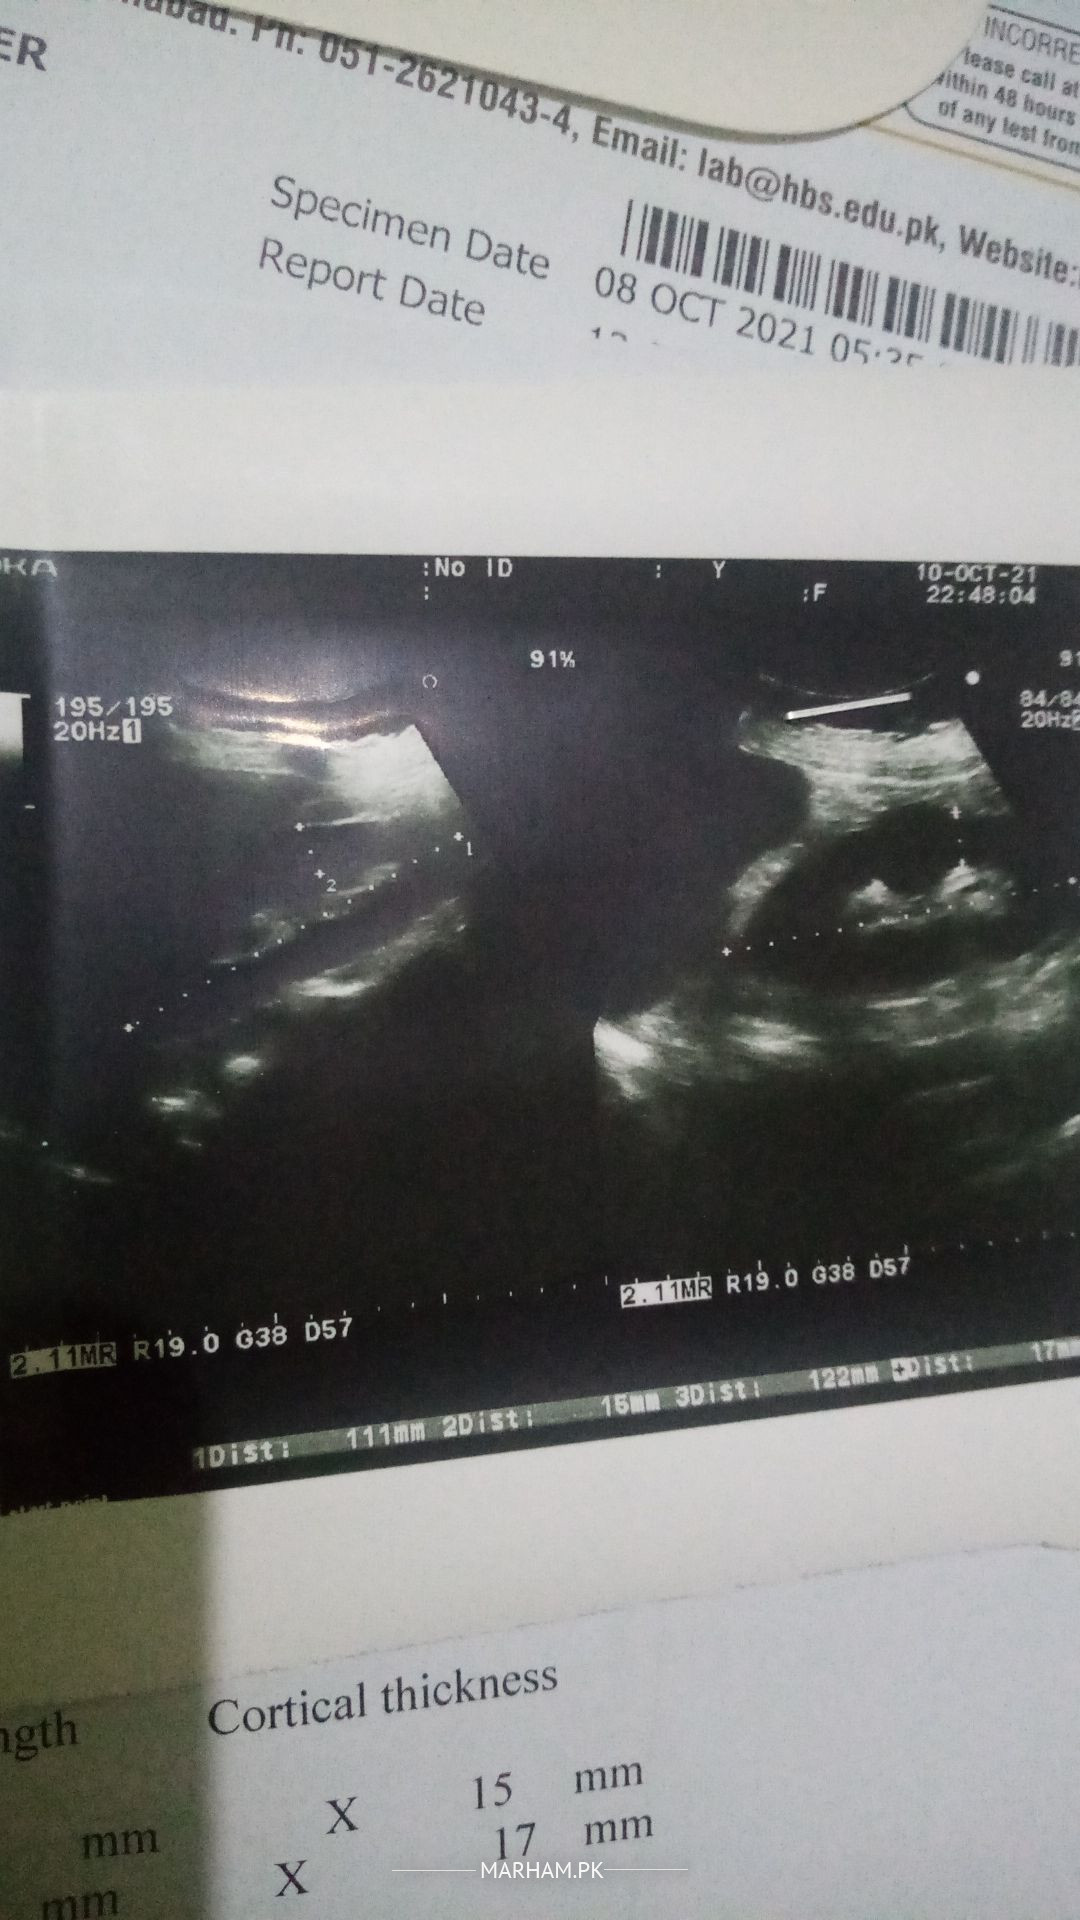

Asking For Mother, Female 62, Islamabad

My mother was having severe urine infection, reports of tests and Ultrasound are attached. Sugar is not under control almost 400-500 fasting. Now she is having fever and weakness at its peak. Kindly guide me about urine test reports and Ultrasound. And what to do now and suggest a doctor for diabetes in Islamabad. One more thing vomit is frequent everything she ate comes out even soup. Thanks in advance. Regards